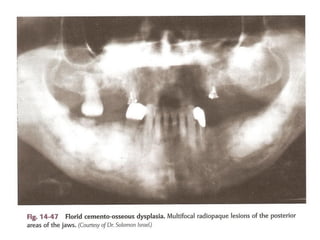

Periapical cemento-osseous dysplasia